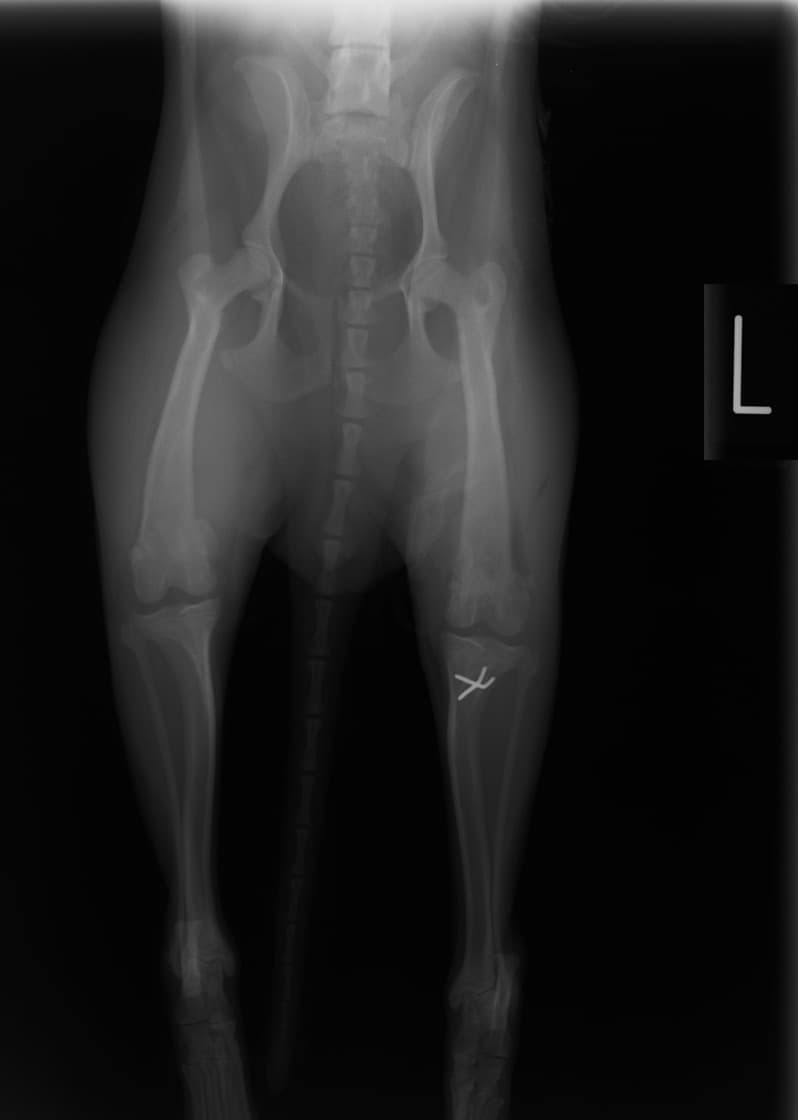

■ 症例22 ポメラニアン 1歳5か月 去勢雄

左後肢の挙上を主訴に来院した。整形学的検査、レントゲン検査より左右の膝蓋骨脱臼(左GradeⅡ〜Ⅲ、右Grade Ⅱ)を認めた。また、脛骨の前方引き出し試験の際に、引き出し兆候は認められないものの、疼痛が認められたため、前十字靭帯の損傷が疑われた。術中における、目視および関節内の操作によって、前十字靭帯の損傷や過伸展といった異常が認められなかったため、膝蓋骨脱臼の整復のみ実施した。手術手技は縫工筋及び内側広筋の解放、脛骨粗面の外側転位、滑車ブロック形造溝術、内外側関節包の縫縮を実施した。本症例は跛行もなく経過良好である。しかし、頸骨高平部の角度(TPA)が 右26.2°、左24.9°であり、解剖学的に前十字靭帯損傷のリスクが高いことから今後の経過に注意が必要である。